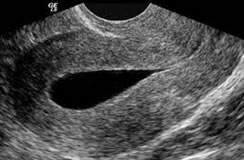

Ecografía Obstétrica

Se usa para diagnosticar la existencia de

embarazo y valorar la situación del embrión o el

feto, así como de la placenta, el útero, cuello

del útero y líquido amniótico. Es el método más

seguro para conocer el estado general del

embarazo y según las semanas de gestación, tiene

sus indicaciones específicas. Entre la 11 y 13

semanas se toma la ecografía genética y entre

las 20 y 24 semanas la morfológica.